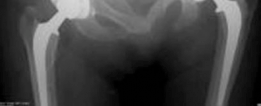

This image depicts a typical hybrid THA construct, showcasing a cemented femoral stem and an uncemented acetabular cup. The distinct fixation mechanisms are visually apparent.